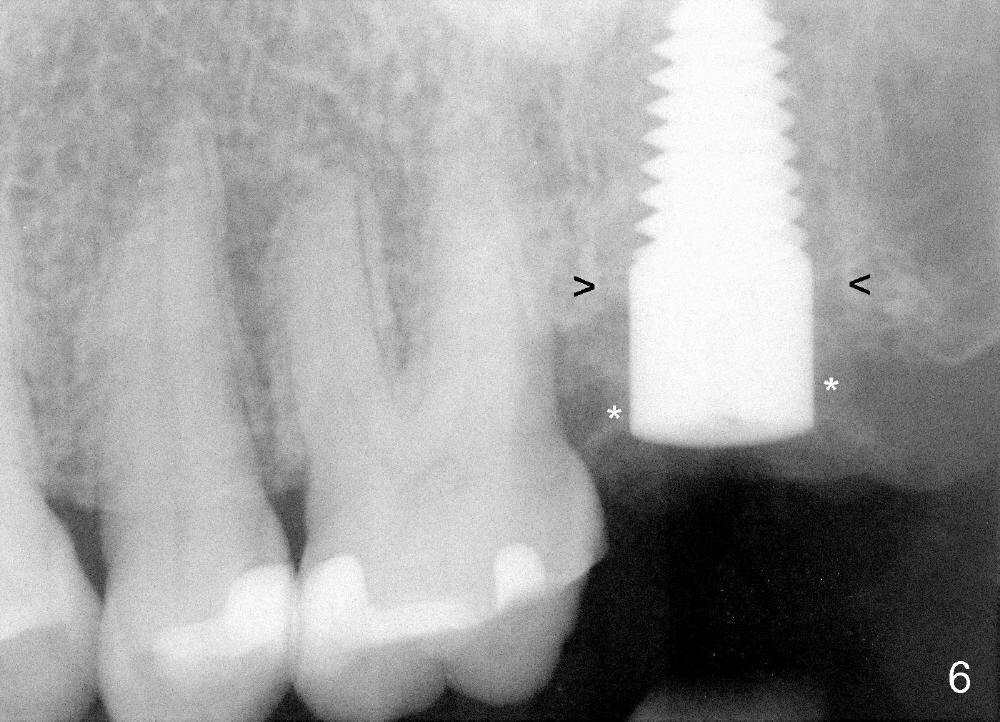

A 57-year-old lady presents for abscess buccal to the tooth #15 (Fig.1 A). Mesial and distal to the occlusal composite (Fig.2 C) is a crack line. In addition to long furcated roots, the upper border of the bone is not shown in this preop PA (arrow). Fig.3 is taken to show a thin septum surrounded by the mesiobuccal (MB), distobuccal (DB) and palatal (P) sockets (Fig.3). Osteotomy is initiated in the septum by 1.2 and 1.5 mm pilot drills, followed by 2,3,4 mm rounded tapered osteotomy at the depth of 17 mm. Nose blowing test is carried out after each step with negative result. Stability is achieved when a 4.5 mm tap is inserted at 17 mm, but the upper end of the tap is not visible (Fig.4,5). When a 5 mm tap is placed, stability is decreased, probably because the coronal end of the septum starts to break down (due to expansion). To re-gain stability, the 5 mm tap needs to go deeper. A 6 mm tap also achieves satisfactory stability at 20 mm. When the tap is removed, there is no air leakage. A 6x20 mm implant is placed with insertion torque > 60 Ncm; the upper end of the implant is still out of view in PA (Fig.6). Another problem is that the implant needs to go deeper to obtain sufficient occlusal clearance. The lower first molars and the 2nd premolars are missing. A panoramic X-ray has to be taken to show the apical end of the implant: ~ 3 mm into the sinus (Fig.7 ^). The maxillary tuberosity appears to grow downward (arrow). In other word, the tooth #15 appears to have been intruded due to overloading.